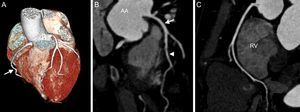

RECENT TECHNICAL DEVELOPMENTWith the introduction of multidetector technology in 1999, visualization of the coronary artery tree at low heart rates became feasible.9 Since then, computed tomography (CT) technology has evolved rapidly, including an increasing number of detectors of up to 392 rows, the introduction of dual-source-CT technology, or increasing pitch factors, enabling image data acquisition in a single heartbeat.10 The increasing spatial resolution of up to approximately 0.5mm allows assessment of the coronary arteries, as well as the presence of plaque and stenosis. Major currently-available technical improvements include imaging at low voltage and high-pitch factors, as well as the introduction of iterative reconstruction (IR) algorithms (Figure 1).

Cardiac computed tomography angiography of a 47-year-old man presenting with atypical chest pain syndrome and known hyperlipidemia. Prospective, elecrocardiogram-triggered computed tomography angiography (100kV, 2.1 mSv) demonstrates a right dominant coronary artery system on volume-rendered images (A, arrow). B: Curved multiplanar reconstruction shows no evidence of coronary plaque or stenosis in the left main coronary artery (arrow), or left anterior descending coronary artery (arrowhead). Similarly, no coronary plaque or stenosis is detected in the right coronary artery (C). AA: ascending aorta; RV: right ventricle.